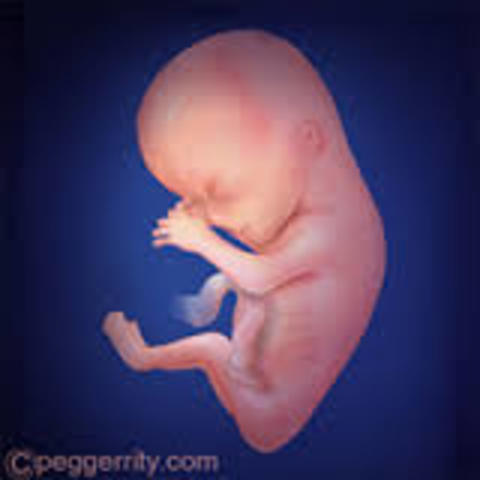

Hacia el final de esata semana, el cuerpo estara formado haci como todos sus organos y terminara el periodo embrionario. Dejara de ser un embrion para combertirce en feto, en esta semana crecen los dedos de las manos y de los pies. La cabeza es desproporcionalmente grande y constituye la mitad del embrion. La region del cuello se a formado, su crecimiento en el utero se ve facilitado por tener un cuerpo muy flexible, su esqueleto no tiene huesos si no cartilago.

• Semana 9

Inicia el periodo fetal, que termina hasta el nacimiento, comienzan a diferenciarce los caracteres sexuales primarios, determinados por la combinacion de coromososmas, heredada en el momento de la fecundacion. Los huesos empiezan a formarce asi como la lengua. Los ojos aun siguen cerrados, Los intestinos se encuntran en el cordon umbilical.